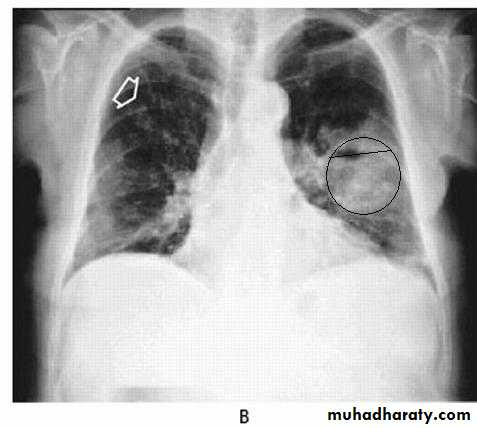

Lung abscess (investigations)

Chest X-ray (and CT scan) shows:homogenous lobar or segmental opacity consistent with consolidation or collapse.

Abscess is characterized by cavitation and fluid level.